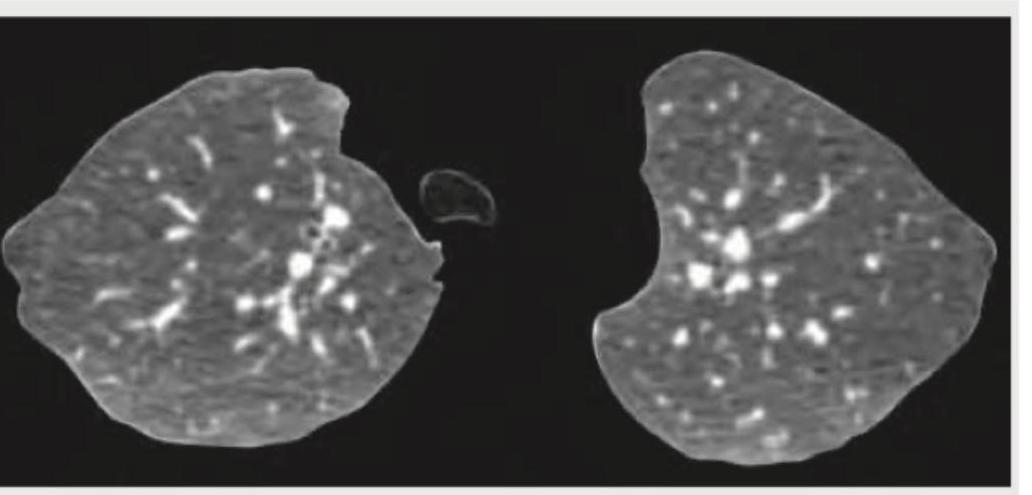

Explanation: ***Crazy pavement pattern*** - The image distinctly shows a combination of **ground-glass opacities** and superimposed **interlobular septal thickening**, which together create the characteristic "crazy paving" appearance. - This pattern is most commonly associated with **pulmonary alveolar proteinosis**, but can also be seen in conditions like ARDS, PCP pneumonia, and lipoid pneumonia. *Honey comb pattern* - This pattern involves the presence of multiple, clustered, thick-walled **cysts** of varying sizes, typically subpleural, which are a sign of **end-stage lung fibrosis**. - While there are cystic changes in the image, the predominant finding includes ground-glass opacities and septal thickening rather than pure end-stage fibrotic changes. *Signet ring pattern* - A signet ring pattern is classically seen in **bronchiectasis**, where a dilated bronchus is paired with its accompanying smaller pulmonary artery, resembling a signet ring. - The image does not show clearly dilated bronchi adjacent to pulmonary arteries; instead, it displays diffuse parenchymal changes. *Mosaic pattern* - The mosaic pattern refers to areas of differing lung attenuation, often due to **air trapping** (causing dark areas) or areas of **perfusion abnormalities** (creating lighter areas), common in conditions like small airway disease or chronic thromboembolic disease. - While there is some heterogeneity, the specific combination of ground-glass and septal thickening is more accurately described as crazy paving.